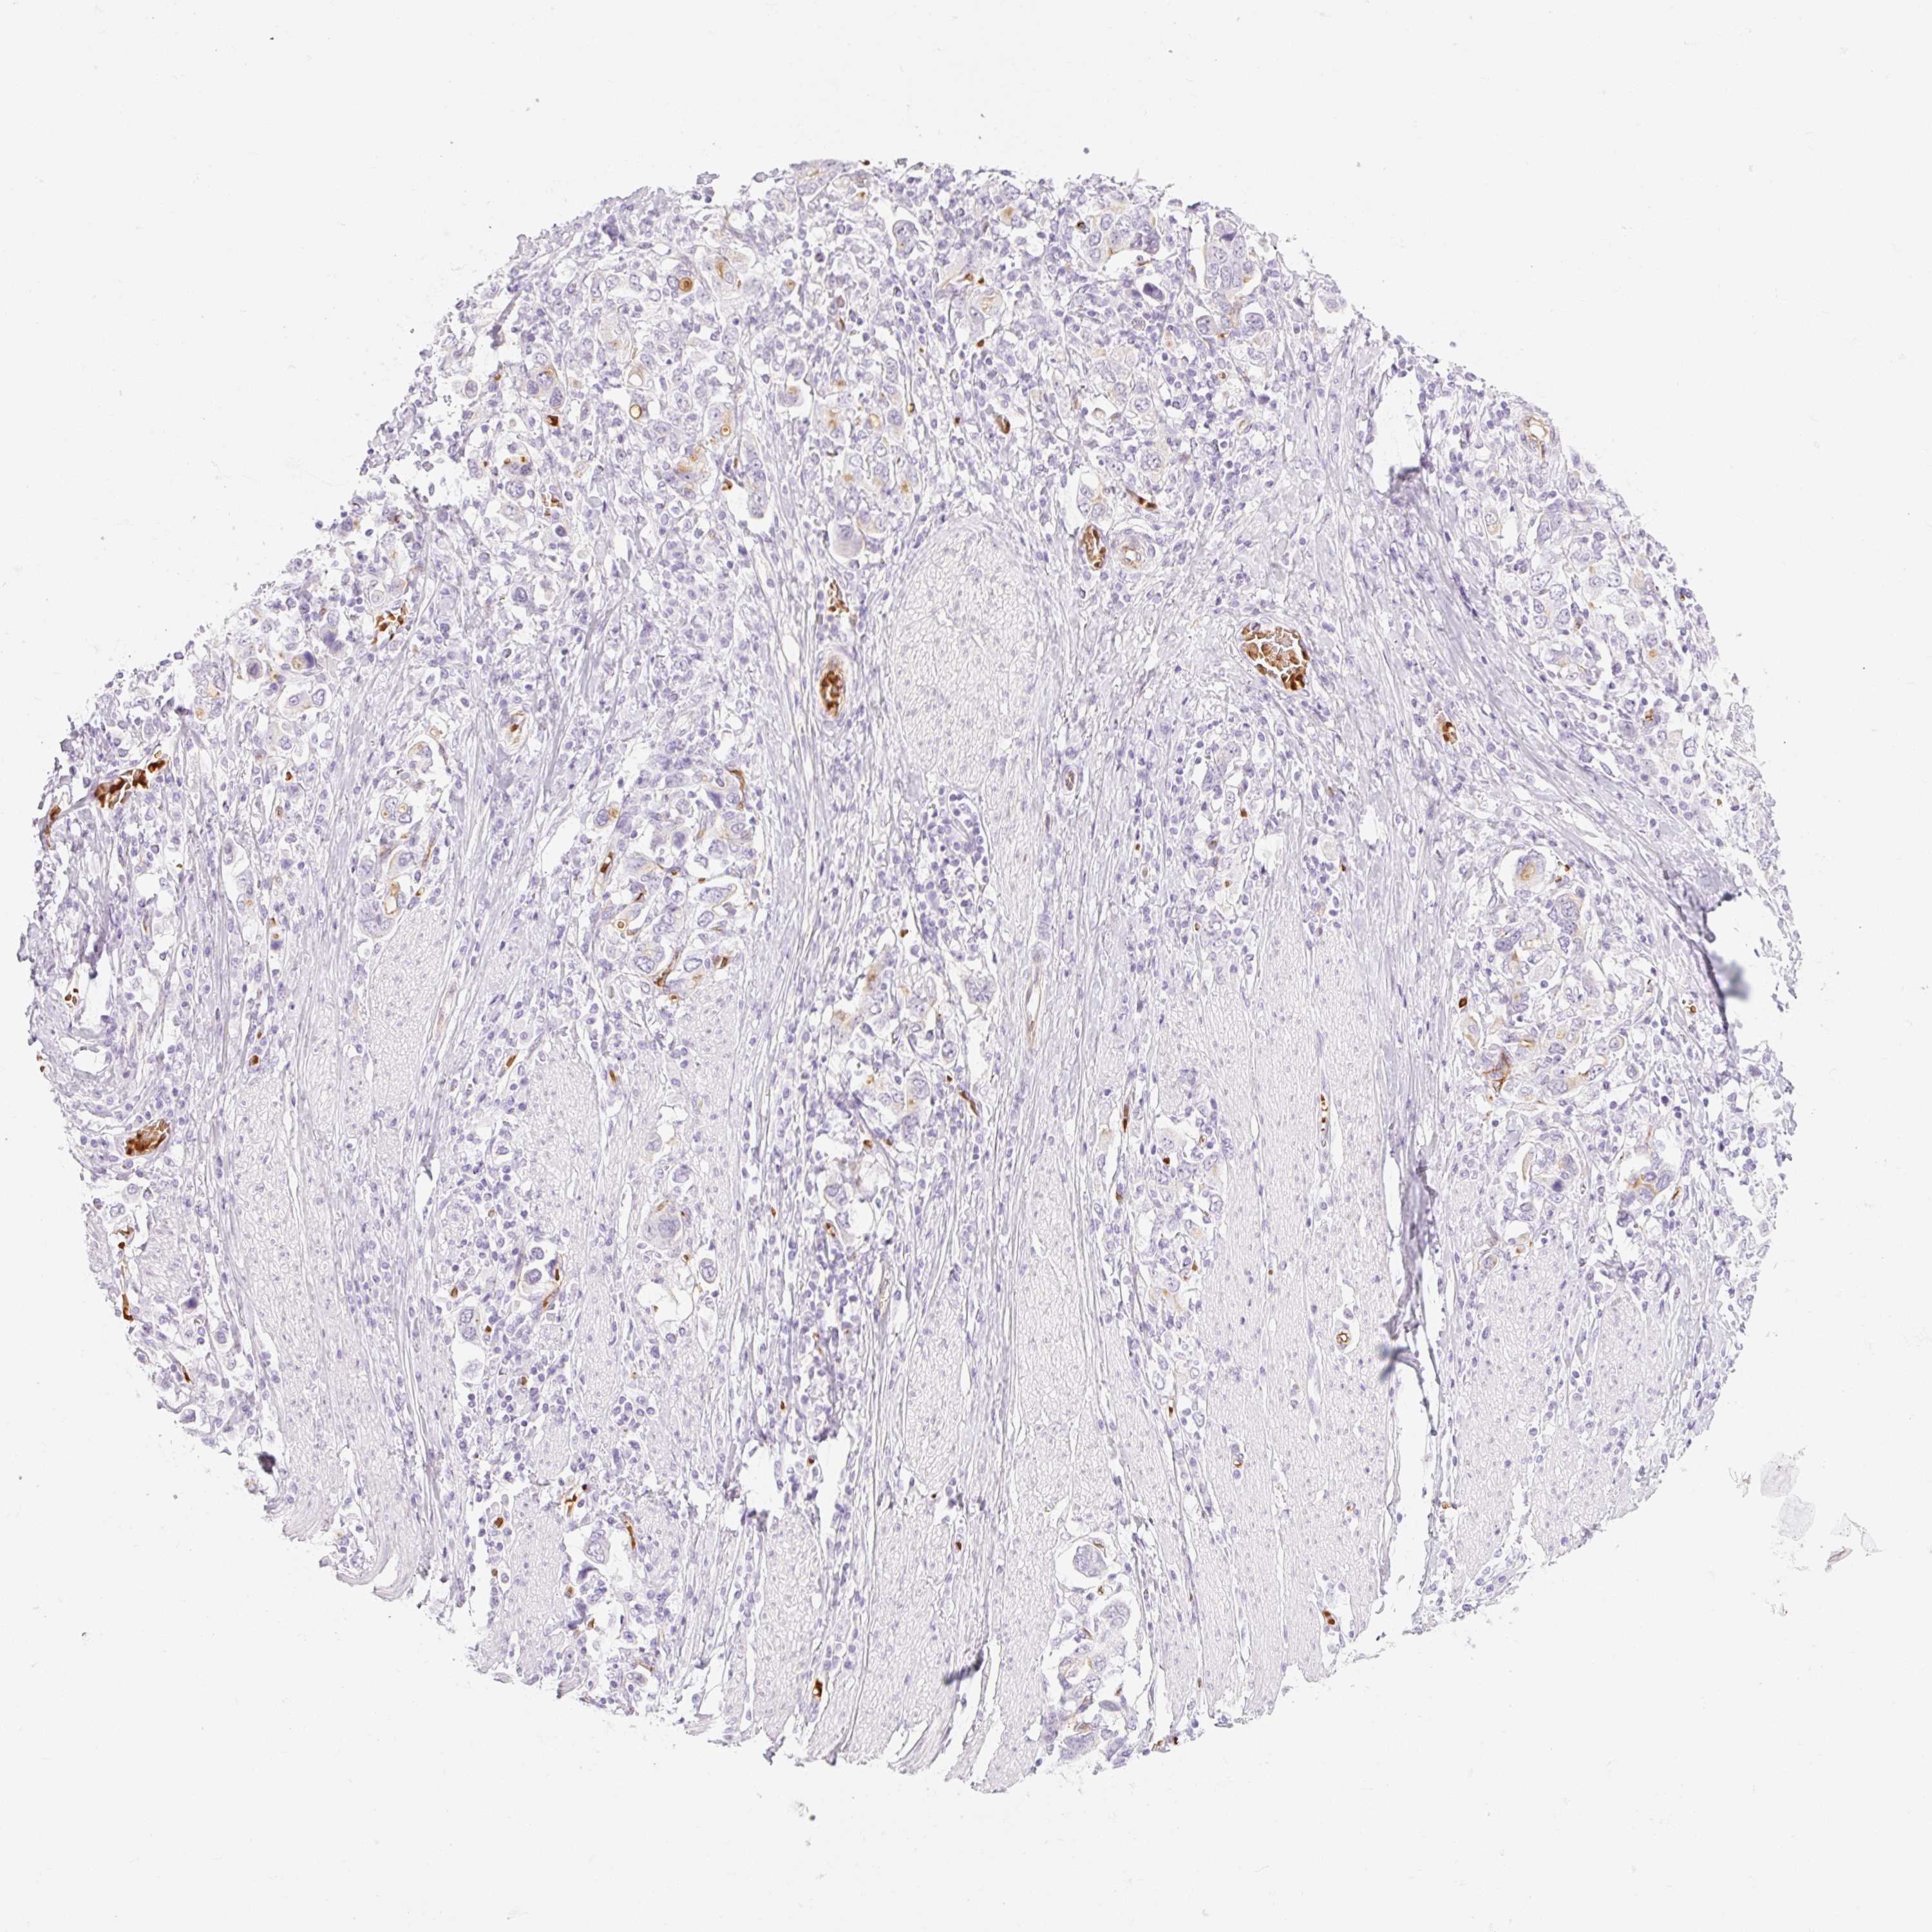

STOMACH CANCER - Protein expressioni

A mouse-over function shows sample information and annotation data. Click on an image to view it in a full screen mode. Samples can be filtered based on level of antibody staining by selecting one or several of the following categories: high, medium, low and not detected. The assay and annotation is described here.

Antibody stainingi

Antibody staining in the annotated cell types in the current human tissue is reported as not detected, low, medium, or high, based on conventional immunohistochemistry profiling in selected tissues. This score is based on the combination of the staining intensity and fraction of stained cells.

Each image is clickable and will lead to virtual microscopy that enables deeper exploration of all samples and also displays staining intensity scores, fraction scores and subcellular localization as well as patient and tissue information for each sample.

Antibody HPA056605

Staining

High

Medium

Low

Not detected

Intensity

Strong

Moderate

Weak

Negative

Quantity

>75%

75%-25%

<25%

None

Location

Nuclear

Cytoplasmic/membranous

Cytoplasmic/membranous,nuclear

Adenocarcinoma, NOS